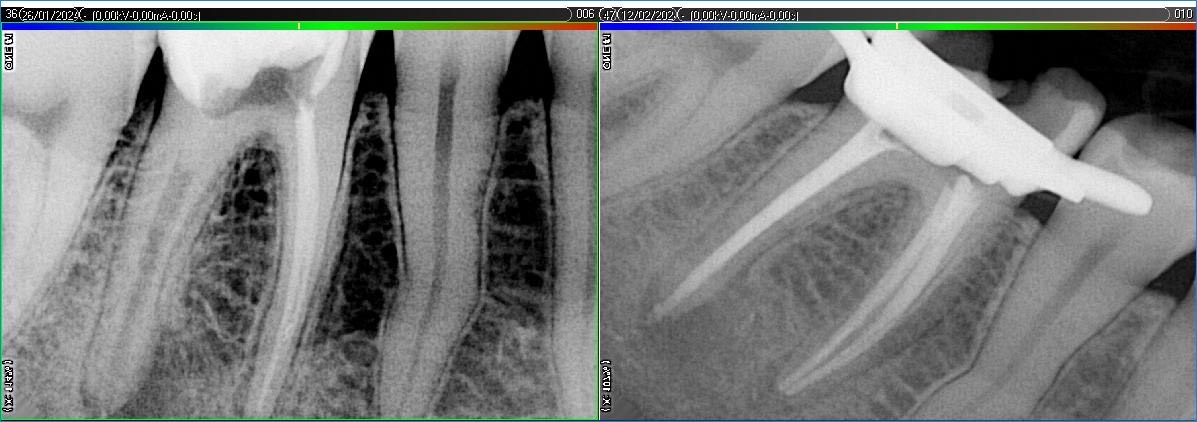

Вилучення інструменту з каналів зуба